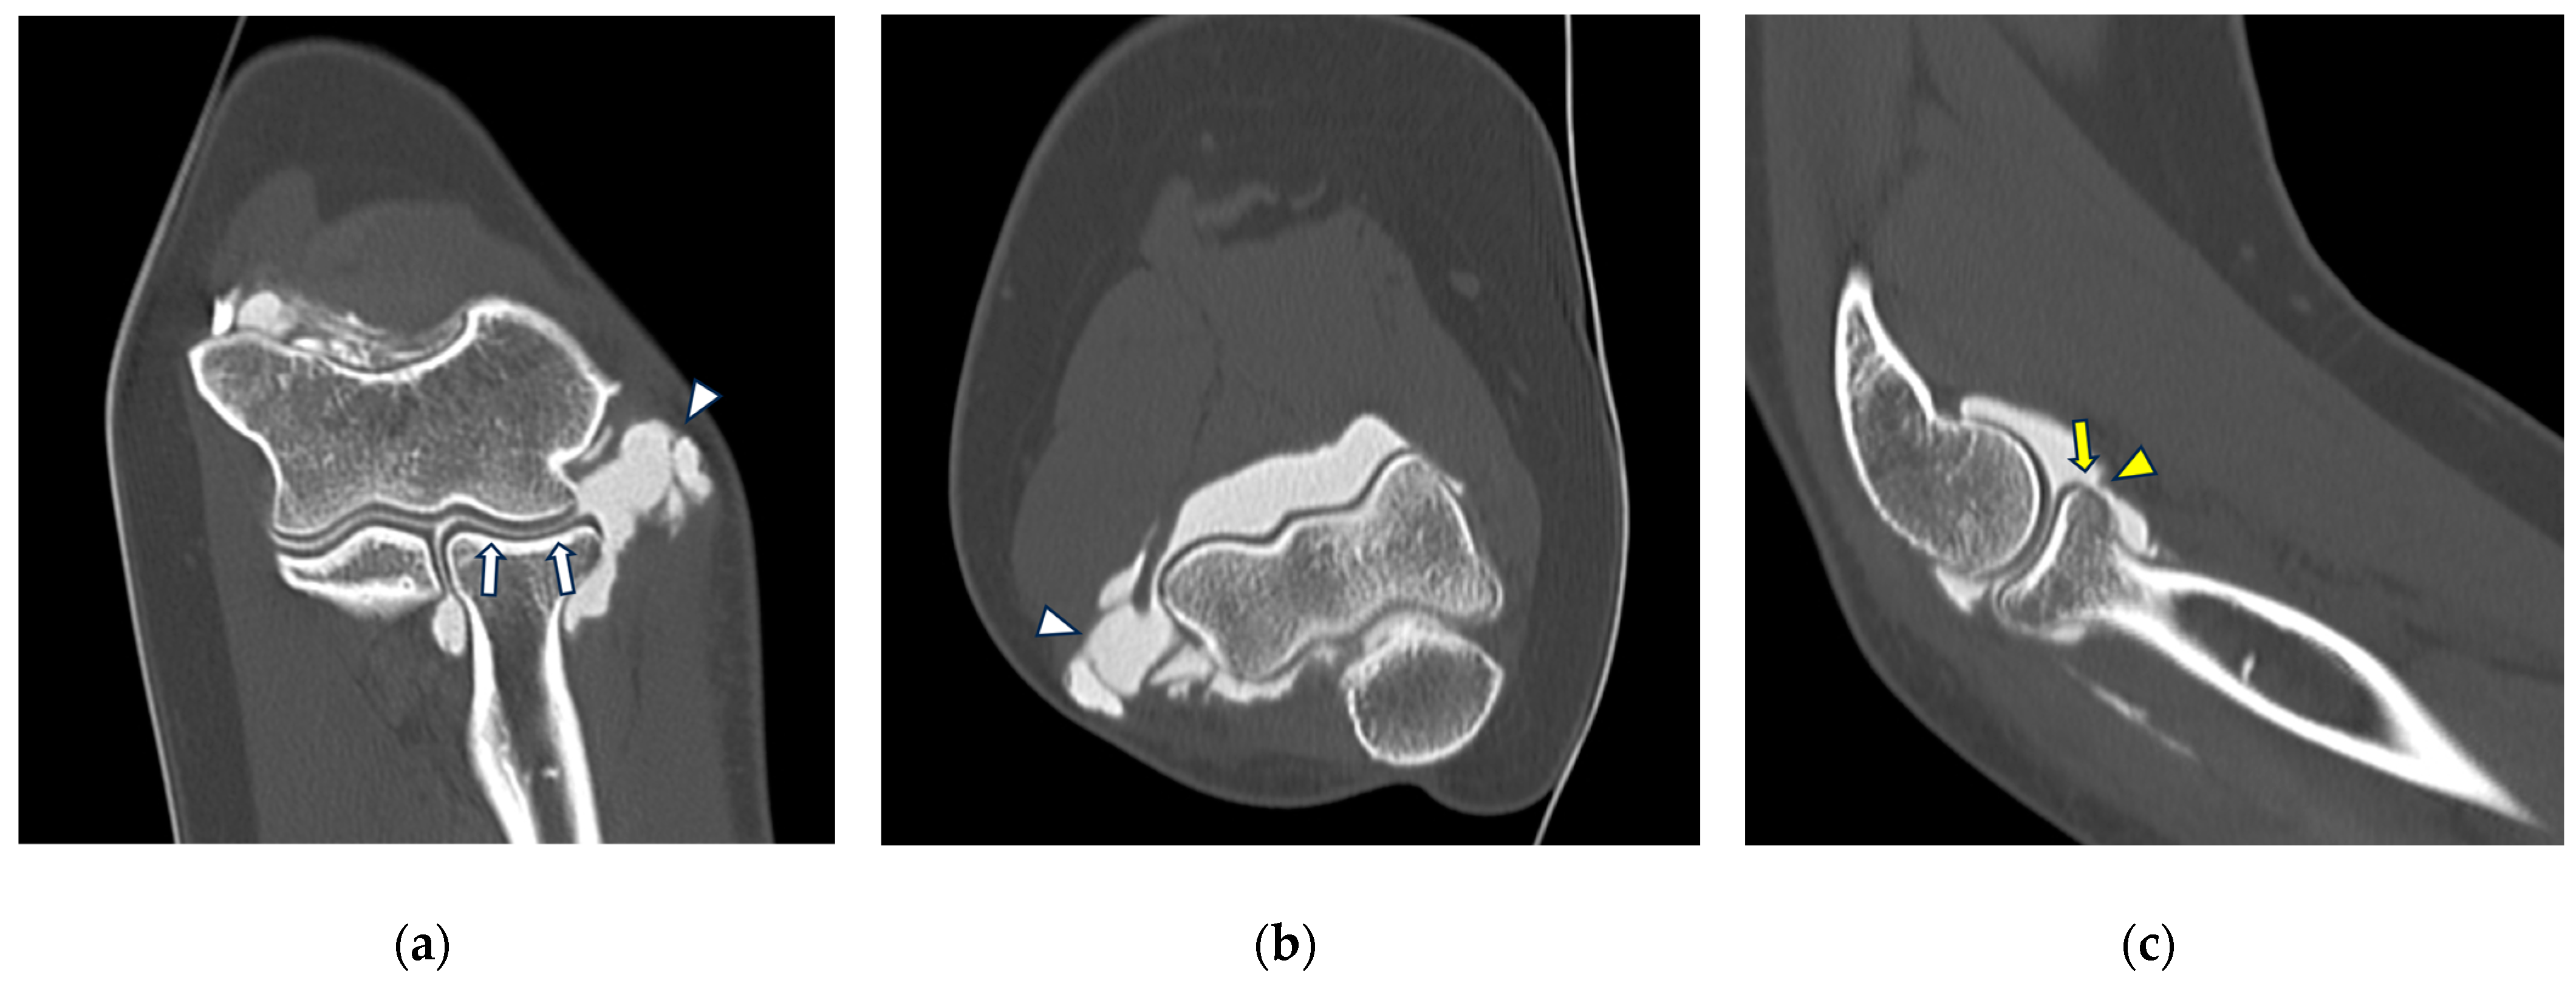

Figure 5.

CT arthrography of a patient with sequelae of traumatic elbow dislocation. (a,b) Coronal and axial images showing LCL laxity with subtle foci of contrast medium permeation due to ligament delamination (white arrowheads) and a loose body within a pathologically distended lateral recess (white arrow), as well as cartilage thinning and fraying of the lateral aspect of the capitulum humeri (yellow arrowhead). Post-traumatic deformity of the radial head can also be seen; (c) sagittal reformat shows a loose bony fragment posterior to the capitulum humeri (asterisk) and posterior synovial thickening (yellow arrow).